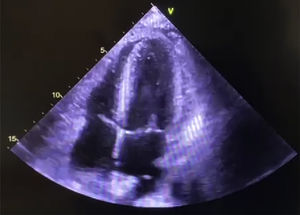

El 15 de marzo presentó angina típica no relacionada con esfuerzo físico, acompañado de diaforesis y disnea, acudió a valoración médica hasta el 21 de marzo del 2022, en la exploración física se ausculta soplo paraesternal izquierdo holosistólico intensidad IV/VI, el electrocardiograma con elevación del segmento ST anterior extenso compatible con infarto del miocardio, ecocardiograma transtorácico mostró pérdida de continuidad de septum interventricular apical, hipocinesia medio apical con fracción de expulsión del ventrículo izquierdo (FEVI), de 45%. Se establece diagnóstico de defecto del tabique interventricular muscular postinfarto de 14 mm con flujo izquierda-derecha. El cateterismo documentó enfermedad ateromatosa significativa univascular de la coronaria descendente anterior (DA), con obstrucción total inmediatamente después de único ramo diagonal, flujo distal TIMI 0, el ventriculograma izquierdo con acinesia anteroseptal y apical, D2VI 28 mmHg, sin regurgitación mitral, se confirma defecto septal apical con cortocircuito izquierda derecha, FEVI 40%. Se decide colocación de balón intraaórtico de contrapulsación e ingreso a terapia intensiva. Se presenta en sesión médico-quirúrgica, donde es aceptado para cierre quirúrgico del defecto interventricular. El 24 de marzo de 2022 se procede a cierre quirúrgico del defecto con parche de pericardio bovino. Presentó lesión renal aguda con recuperación de la misma, la estancia en terapia intensiva fue de 10 días y egresado 15 días de postoperatorio. El 5 de mayo de 2022 presentó datos de insuficiencia cardiaca aguda en clase funcional (CF) NYHA IV, e INTERMACS 4, retención hídrica, disnea al mínimo esfuerzo, ortopnea, disnea paroxística nocturna, edema de tobillos, por lo que se realizó nuevo ecocardiograma que mostró comunicación interventricular residual por desprendimiento del parche en zona distal, con flujo izquierda/derecha (fig. 1).

El ecocardiograma realizado el 19 de septiembre del 2022 muestra del VD 20 mm, diámetro diastólico del VI 47 mm, diámetro sistólico del VI: 35 mm, FEVI: 60%, septum: 9 mm, pared posterior del VI: 10 mm. ITV del TSVI 15 cm.